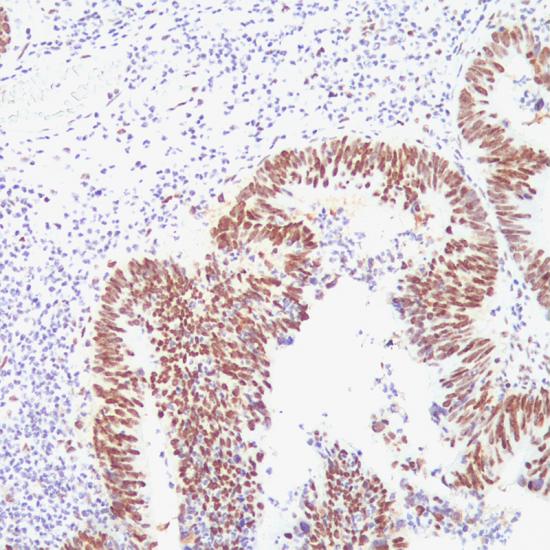

MSH2

MSH2抗體試劑(免疫組織化學(xué)) 閩廈械備20180076號

細(xì)胞核

結(jié)腸癌

石蠟

G219-1129

MSH2是一種錯配修復(fù)基因,突變后會使細(xì)胞錯配修復(fù)功能缺陷,導(dǎo)致微衛(wèi)星不穩(wěn)定,使腫瘤易感。通常和MLH1、MSH6、PMS2一起用于腫瘤的研究。